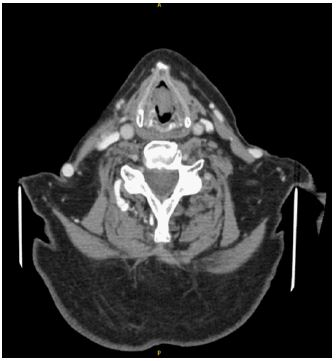

An urgent CT neck with intravenous contrast was organized to further characterize the mass. Images revealed an exophytic polypoid lesion originating at the level of the glottis measuring 1.8(AP)×1.0(LL)×2.1(CC) cm (Figure 1). The lesion extended to occupy most of the airway causing significant narrowing of the airway itself but there was no evidence of infiltration of surrounding structures. There was no lymphadenopathy by CT size criteria in the neck.

Figure 2: Contrast enhanced CT neck in axial view demonstrating lesion at the level of the glottis.

Radiologically nodular fasciitis identifies as a well demarcated homogenous area of low to moderate enhancement on contrast enhanced computed tomography. It is reported to spread in different planes both radiologically and in terms of histocytology [3,6]. As per (Figure 2) below, we report a single-phase CT with the lesion showing minimal extension into the subglottic plane as well as cranial extension into the ventricle. There is no convincing evidence of deep extension into the paraglottic spaces laterally.